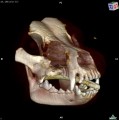

CT - lebka